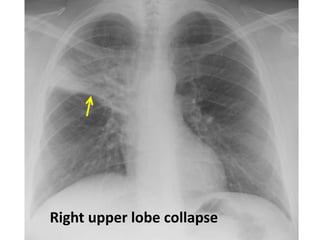

Right upper lobe collapse

and consolidation . Lobar

density . Air bronchogram .

RUL infiltration with air bronchogram +

atelectasis

Right upper lobe collapse .

Segmental or lobar density

Compensatory hyperinflation of

normal lung

Right upper lobe

collapse